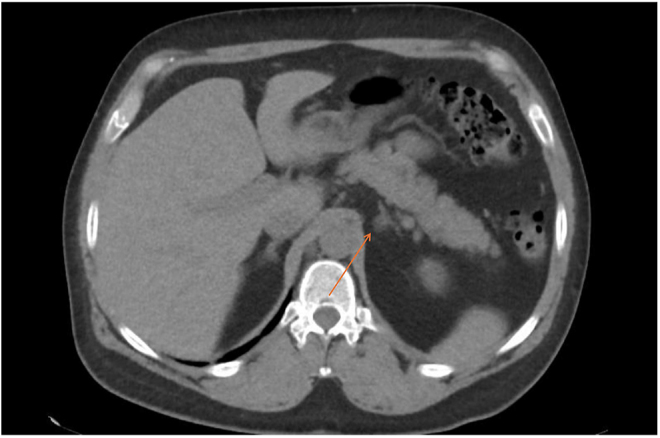

Summary: We describe a case of a 42-year-old gentleman, 5 years post-transsphenoidal surgery (TSS) for pituitary-dependent Cushing's disease, initially presenting with malignant hypertension. Despite an initial improvement in his blood pressure post-TSS, he was found to be persistently hypertensive on follow-up despite no clinical or biochemical evidence of recurrence of hypercortisolism. His blood pressure remained elevated despite five antihypertensive agents. His renin concentration was <5 mIU/L (9-103.5) and aldosterone concentration was 877 pmol/L (0-670). A subsequent CT of the adrenals showed a 1.2 cm left adrenal nodule. He was not suitable for adrenal vein sampling (AVS) at this time due to difficult-to-control hypertension. Biochemistry was difficult to interpret in the context of a multitude of interfering medications, which were necessary given his difficult-to-control hypertension and hypokalaemia. Once suitable, his initial AVS was unsuccessful due to failure to cannulate the right adrenal vein. He was given the further options of repeat AVS vs 11C-metomidate PET vs medical management of his blood pressure. He proceeded with a repeat AVS, with successful cannulation of both adrenal veins. This showed evidence of hyperaldosteronism on the left side, with a lateralisation index of 39.5 and a contralateral suppression index of 0.28. He proceeded with a robotic left adrenalectomy, leading to significant improvement in his blood pressure, dropping from a mean reading of 142/85 during daytime and 150/88 mmHg at nighttime on five antihypertensive agents to normotensive levels of 114/77 mmHg on two agents.